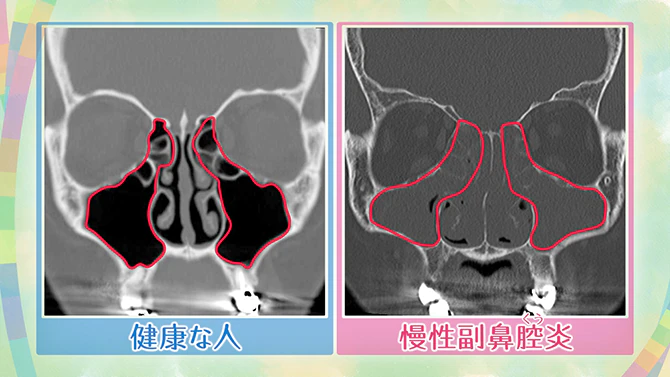

- 화상 검사

CT에 의한 화상 검사도 실시해, 부비강의 상태를 조사합니다.

건강한 부비동 (사진 왼쪽)은 공기로 채워지고 CT 이미지에서 검은색으로 찍혀 있습니다. 한편 만성 부비동염이 있으면 부비동에 고름이 쌓여 회색으로 찍혀 있습니다. 염증이 일어나 점막이 붓는 상태입니다. (사진 오른쪽).